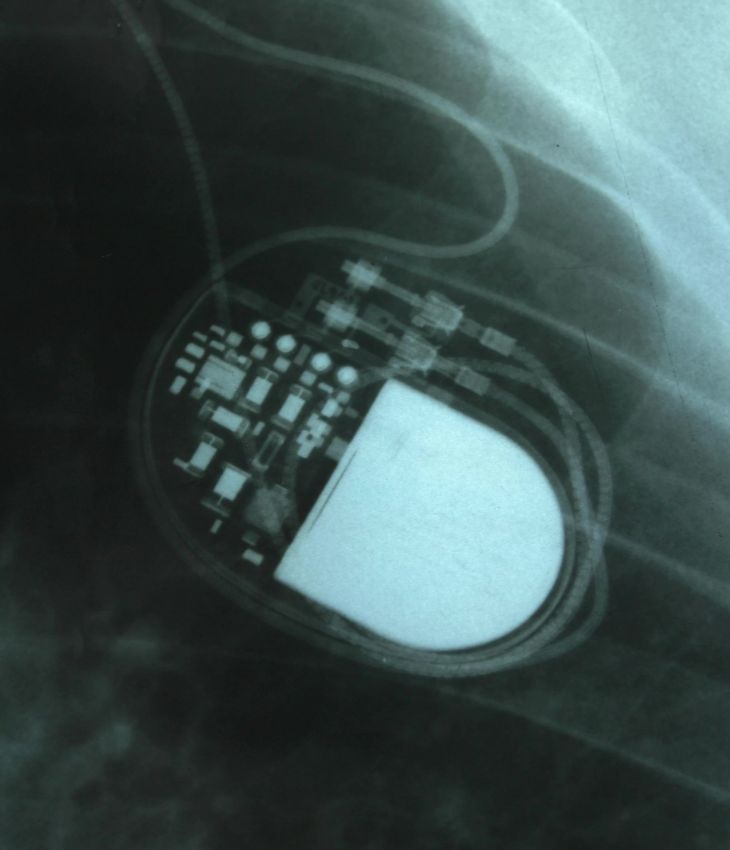

A pacemaker is a device that sends electrical impulses to regulate your heart rate. It is implanted under the skin, usually just below the collarbone, and connected to the heart via small wires called leads.

Pacemaker insertion is a straightforward procedure used to treat bradycardia (slow heart rhythm) or pauses in the heartbeat. It ensures your heart beats at a regular pace, helping to relieve symptoms such as dizziness, fatigue, or blackouts. The procedure is typically done under local anaesthetic with light sedation.